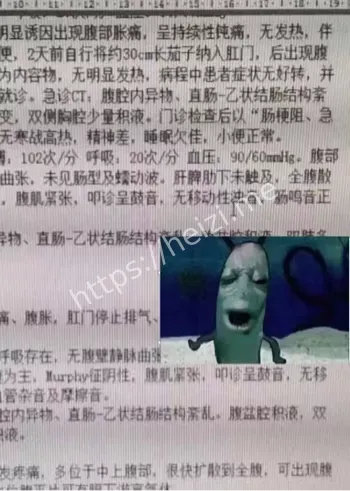

重点来了,这茄子可不是一般的茄子,30cm长,卡在直肠里,取出来可费了医生老大劲!据说大叔疼得满头大汗,医生也是满脸问号,手术室里气氛一度尴尬到爆。网友们在网上吵翻了,有人好奇“咋塞进去的”,有人直呼“这操作太野了”!还有人脑洞大开,猜是不是大叔在家做啥“实验”失败了? 直肠藏30cm茄子这关键词,绝对是热搜榜的潜力股。网友们一边吃瓜一边吐槽,纷纷表示这事儿太离谱,简直刷新认知底线。但说真的,这背后到底是啥情况?

医院操作引关注:医生的心理阴影有多大?

再说说医院这边,医生们估计也是满头黑线。据爆料,急诊科接到这病例时都懵了,手术过程小心翼翼,硬是把30cm茄子给取出来了!有网友调侃:“医生这波操作,心理阴影面积得有几平米吧?”还有人感慨:“医护人员太不容易了,啥病例都得面不改色!”这事儿也让大家好奇,医院咋处理的?会不会有官方通报? 深夜急诊、奇葩事件这些关键词,直接戳中吃瓜群众的兴趣点。医院的处理方式也成了讨论焦点,有人猜大叔会不会被医院“拉黑”,也有人关心后续医疗费用咋算。